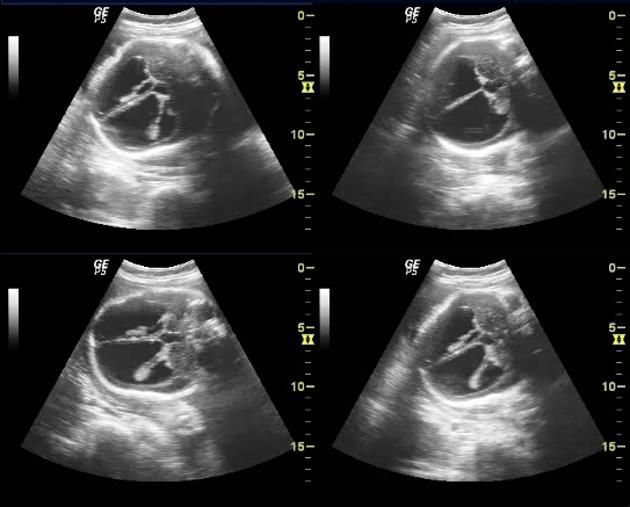

Hydrocephalus Definition Hydrocephalus is a condition in which excess cerebrospinal fluid (CSF) builds up within the fluid-containing cavities or ventricles of the brain. The term hydrocephalus is derived from the Greek words "hydro" meaning water and "cephalus" meaning the head. Although it translates as "water on the brain," the word actually refers to the buildup of cerebrospinal fluid, a clear organic liquid that surrounds the brain and spinal cord. CSF is in constant circulation within the ventricles of the brain and serves many crucial functions: 1) it acts as a "shock absorber" for the brain and spinal cord; 2) it acts as a vehicle for delivering nutrients to the brain and removing waste from it; and 3) it flows between the cranium and spine to regulate changes in pressure. When CSF builds up around the brain, it can create harmful pressures on the tissues of the brain confined within the skull. The accumulation of CSF occurs due to either an increase in production of the fluid, a decrease in its rate of absorption or from a condition that blocks its normal flow through the ventricular system. Hydrocephalus can occur at any age, but is most common in infants and adults age 60 and older. According to the National Institute of Neurological Disorders and Stroke (NINDS), hydrocephalus is believed to affect approximately one to two in every 1,000 children born in the U.S. The majority of these cases are often diagnosed before birth, at the time of delivery or in early childhood. Causes Little is understood about the causes of hydrocephalus. Some cases of hydrocephalus are present at birth, while others develop in childhood or adulthood. Hydrocephalus can be inherited genetically, may be associated with developmental disorders, like spina bifida or encephalocele, or occur as a result of brain tumors, head injuries, hemorrhage or diseases such as meningitis. Based on onset, presence of structural defects or high vs. normal CSF pressures, hydrocephalus can be divided into categories. Acquired Hydrocephalus: This is the type of hydrocephalus that develops at birth or in adulthood and is typically caused by injury or disease. Congenital Hydrocephalus: It is present at birth and may be caused by events that occur during fetal development or as a result of genetic abnormalities. Communicating Hydrocephalus: This type of hydrocephalus occurs when there is no obstruction to the flow of CSF within the ventricular system. The condition arises either due to inadequate absorption or due to an abnormal increase in the quantity of CSF produced. Non-communication (Obstructive) Hydrocephalus: It occurs when the flow of CSF is blocked along one of more of the passages connecting the ventricles, causing enlargement of the pathways upstream of the block and leading to an increase in pressure within the skull. Normal Pressure Hydrocephalus: It is a form of communicating hydrocephalus that can occur at any age, but is most common in the elderly. It is characterized by dilated ventricles with normal pressure within the spinal column. Hydrocephalus Ex-vacuo: It primarily affects adults and occurs when a degenerative disease, like Alzheimer’s disease, stroke or trauma, causes damage to the brain that may cause the brain tissue to shrink. Symptoms The symptoms of hydrocephalus tend to vary greatly from person to person and across different age groups. Infants and young children are more susceptible to symptoms from increased intracranial pressure like vomiting and adults can experience loss of function like walking or thinking. Infants Unusually large head size Rapidly increasing head circumference Bulging and tense fontanelle or soft spot Prominent scalp veins Downward deviation of eyes or sunset sign Vomiting Sleepiness Irritability Seizures Children and Adolescents Nausea and vomiting Swelling of the optic disc or papilledema Blurred or double vision Balance and gait abnormalities Slowing or loss of developmental progress Changes in personality Inability to concentrate Seizures Poor appetite Urinary incontinence Adults Headache Nausea and vomiting Difficulty walking or gait disturbances Loss of balance or coordination Lethargy Bladder incontinence Impaired vision Impaired cognitive skills Memory loss Mild dementia Testing and Diagnosis Once a physician suspects hydrocephalus, he/she performs a thorough clinical evaluation, including reviewing and recording a detailed patient history and performing a physical exam to assess the condition. A complete neurological examination, including one of more of the following tests, is usually recommended to confirm the diagnosis and assess for treatment options: Computed tomography scan (CT or CAT scan) Magnetic resonance imaging (MRI) Lumbar puncture (spinal tap) Intracranial pressure monitoring Isotope cisternography The tests may reveal useful information about the severity of the condition and its likely cause. Once hydrocephalus is suspected, it is important that a neurosurgeon and/or neurologist become part of the medical team for their expertise on interpreting test results and treating the condition. Treatment Hydrocephalus can be treated in a variety of ways. Based on the underlying etiology, the condition may be treated directly by removing the cause of CSF obstruction or indirectly by diverting the excess fluid. Hydrocephalus is most commonly treated indirectly by implanting a device known as a “shunt” to divert the excess CSF away from the brain. The shunt is a flexible tube which, along with a catheter and a valve, is placed under the skin to drain excess CSF from a ventricle inside the brain to another body cavity such as the peritoneal cavity (the area surrounding the abdominal organs). Once inserted, the shunt system usually remains in place for the duration of a patient's life (although additional operations to revise the shunt system are sometimes needed). The shunt system continuously performs its function of diverting the CSF away from the brain, thereby keeping the intracranial pressure within normal limits. In some cases, two procedures are performed, the first to divert the CSF and another at a later stage to remove the cause of obstruction (e.g. a brain tumor). A limited number of patients can be treated with an alternative operation called endoscopic third ventriculostomy. In this procedure, a surgeon utilizes a tiny camera (endoscope) with fiber optics to visualize the ventricles and create a new pathway through which CSF can flow. Follow-up Neurological function will be evaluated after surgery. If any neurological problems persist, rehabilitation may be required to further improvement. However, recovery may be limited by the extent of the damage already caused by the hydrocephalus and by the brain's ability to heal. Because hydrocephalus is an ongoing condition, long-term follow-up by a doctor is required. Follow-up diagnostic tests, including CT scans, MRIs and x-rays, are help determine if the shunt is working properly. A physician should be contacted if any of the following postoperative symptoms are experienced: Redness, tenderness, pain or swelling of the skin along the length of the tube or incision Irritability or drowsiness Nausea, vomiting, headache or double vision Fever Abdominal pain Return of preoperative neurological symptoms Prognosis The prognosis for hydrocephalus depends on the cause, the extent of symptoms and the timeliness of diagnosis and treatment. Some patients show a dramatic improvement with treatment, while others do not. In some instances of normal pressure hydrocephalus, dementia can be reversed by shunt placement. Other symptoms, such as headaches, may disappear almost immediately if the symptoms are related to elevated pressure. In general, the earlier hydrocephalus is diagnosed, the better the chance for successful treatment. The longer the symptoms have been present, the less likely it is that treatment will be successful. Unfortunately, there is no way to accurately predict how successful surgery will be for each individual. Some patients will improve dramatically, while others will reach a plateau or decline after a few months. Shunt malfunction or failure may occur. The valve can become clogged or the pressure in the shunt may not match the needs of the patient, requiring additional surgery. In the event of an infection, antibiotic therapy may be needed and likely temporary removal of the shunt and replacement by a drain until the infection clears. The shunt can then be re-implanted. A shunt malfunction may be indicated by headaches, vision problems, irritability, fatigue, personality change, loss of coordination, difficulty in waking up or staying awake, a return of walking difficulties, mild dementia or incontinence. In infants, the symptoms of shunt malfunction can include the above as well as vomiting, inappropriate head growth and/or sunsetting eyes. When a shunt malfunctions, surgery is often needed to replace the blocked or malfunctioning portion of the shunt system. Fortunately, most complications can be dealt with successfully.